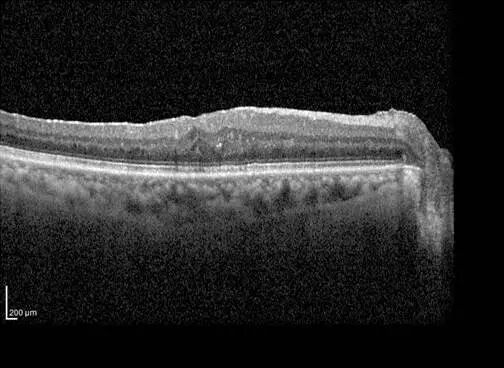

术后:前膜成功剥除,黄斑结构基本恢复平整,水肿基本消退。

治疗前后黄斑区视网膜厚度对比:因黄斑水肿明显消退,视网膜厚度值明显降低。

治疗后